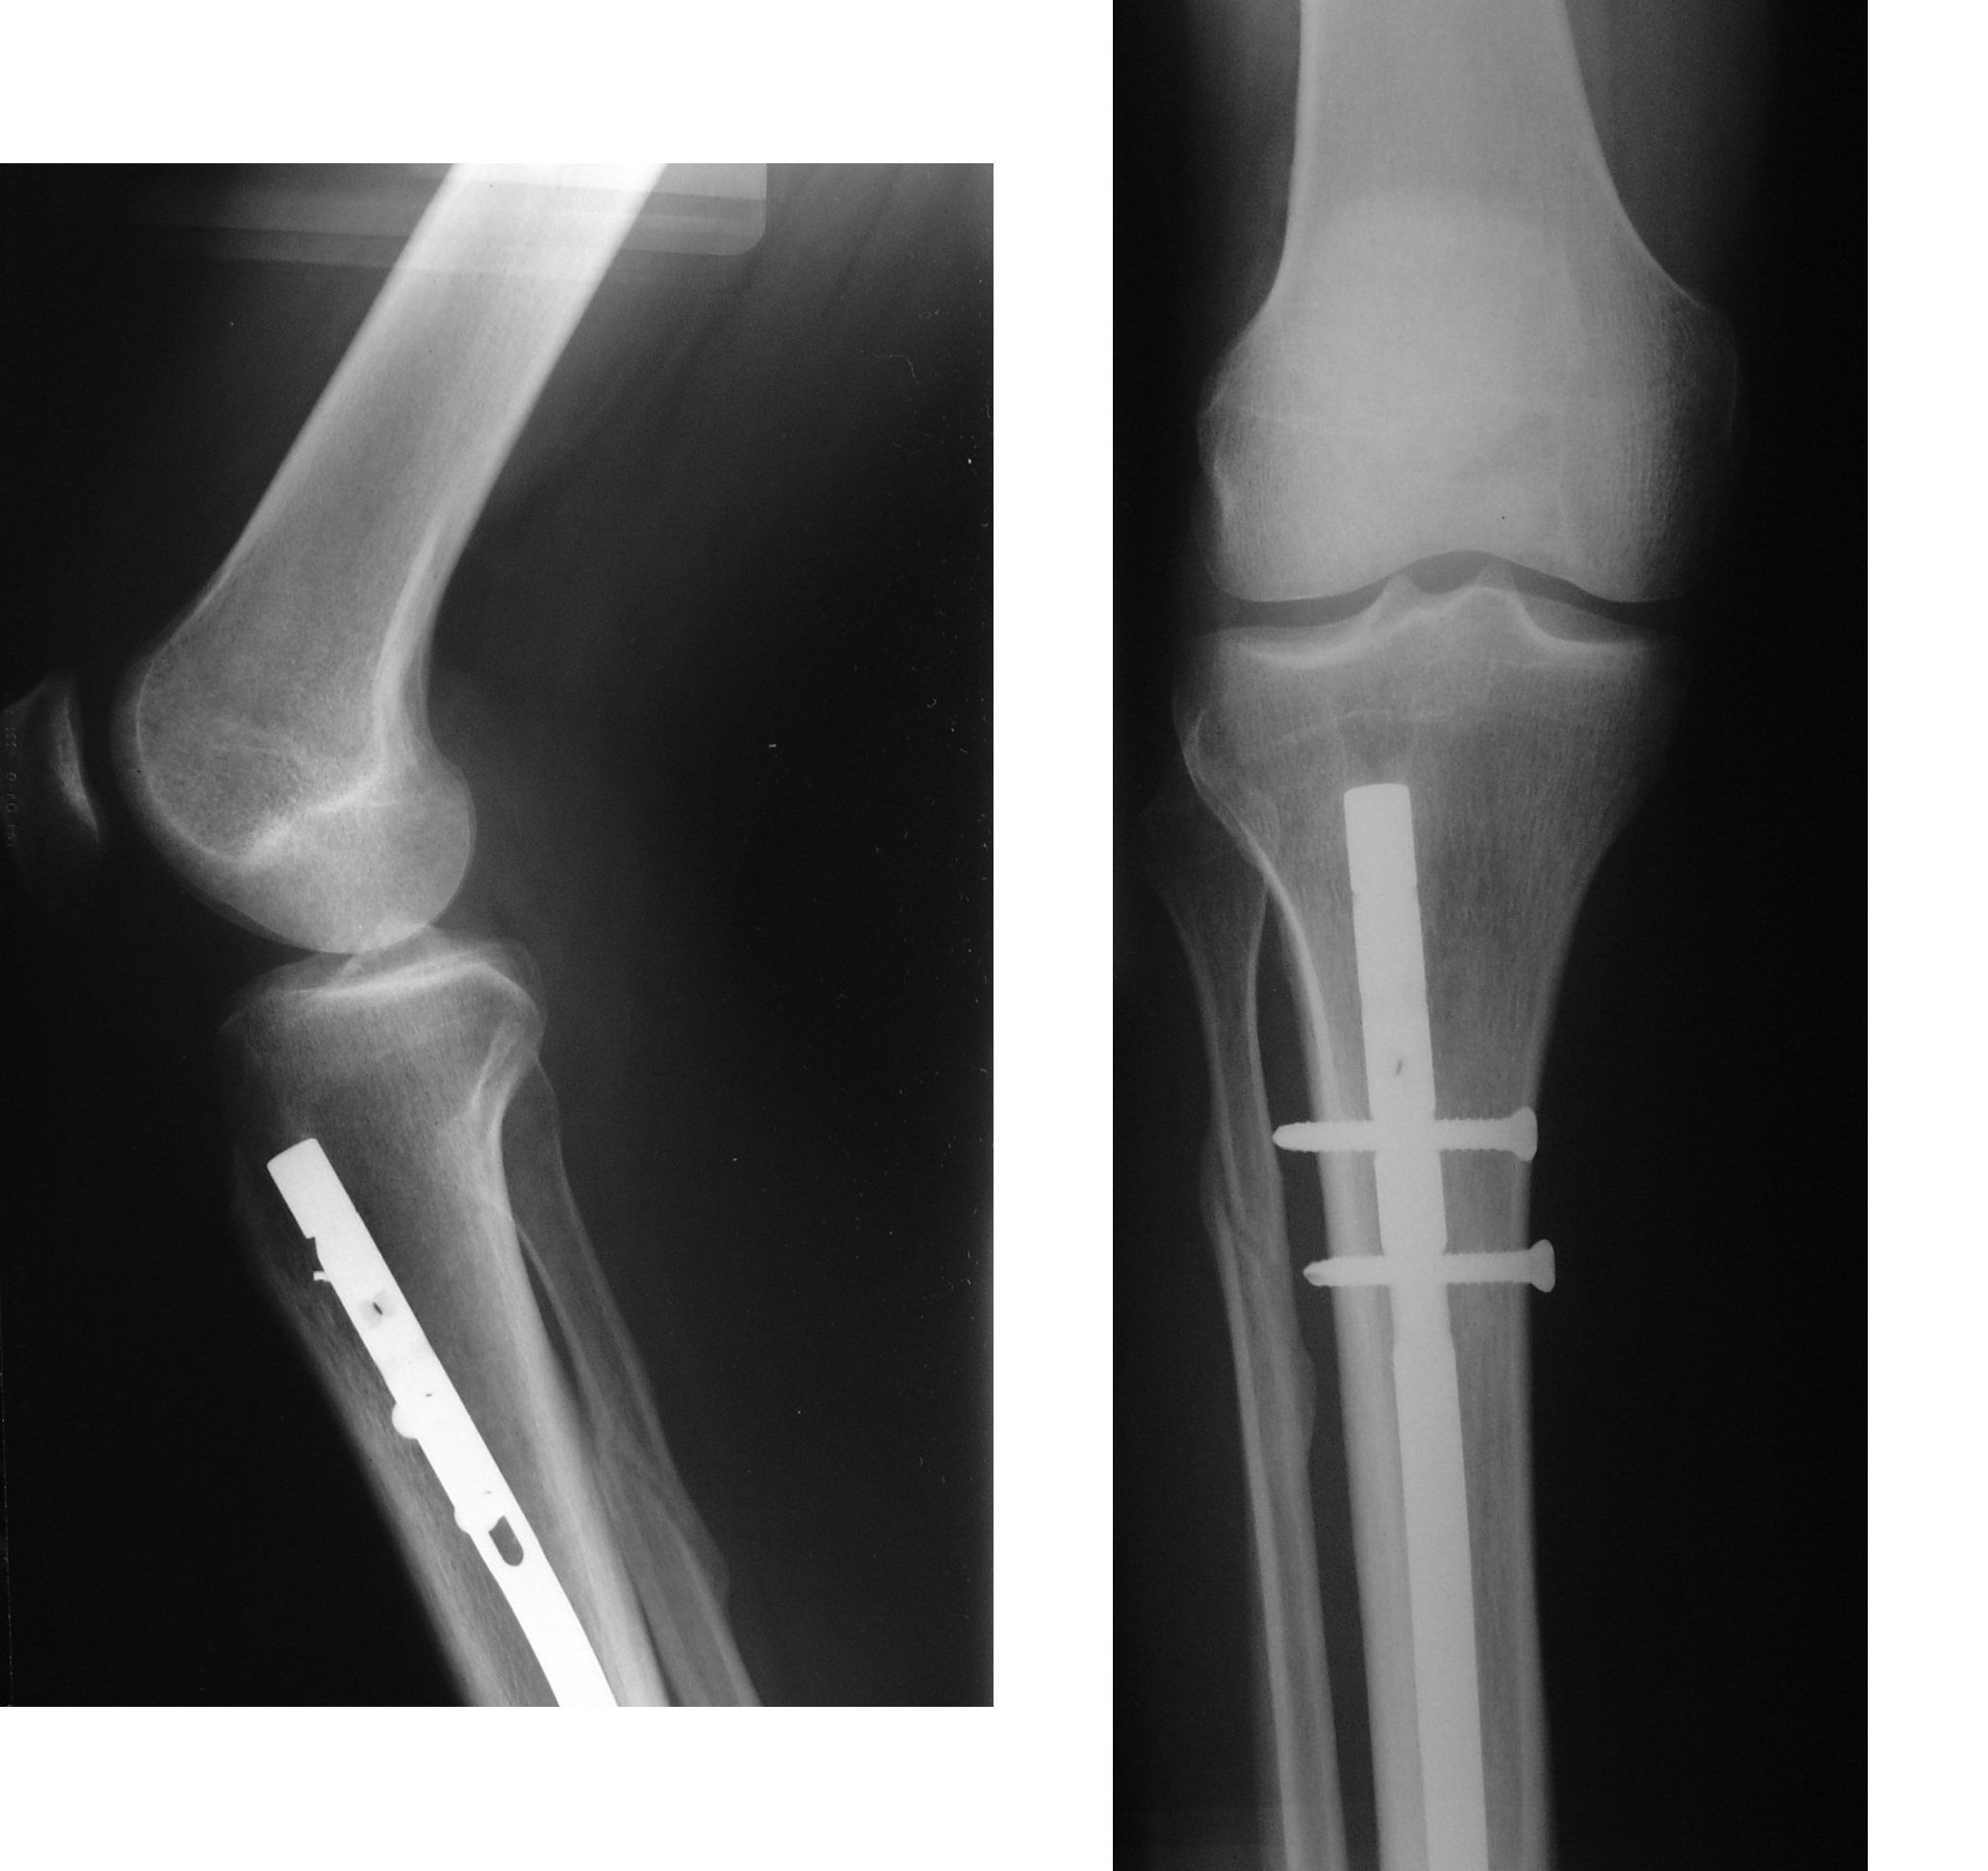

Following are the indications of intramedullary nails for fractures: - transverse midshaft fracture - short oblique midshaft fractures - segmental fractures - pathological fractures Reference: https://journals.healio.com/cms/asset/1e1d7bd0-0864-480a-b823-c99074ce2255/10.3928_01477447-19851101-10-table1.jpg Image via: https://en.wikipedia.org/wiki/Intramedullary_rod